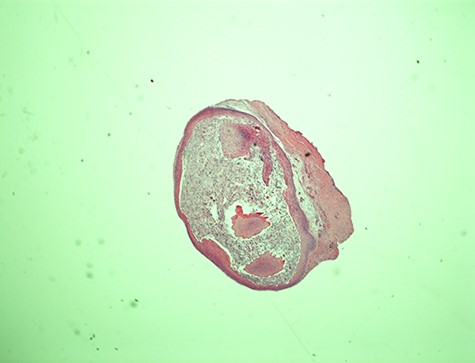

Epidermal cyst—20× magnification. Low power microscopic view of the vocal cord epidermal inclusion cyst. Hematoxylin and eosin (H&E) stain X.

The histopathological features of the right vocal cord cyst were consistent with an EIC of the larynx, whereas the left vocal cord cyst showed minute fragment of benign squamous epithelium and skeletal muscle (Figs 1 and 2).